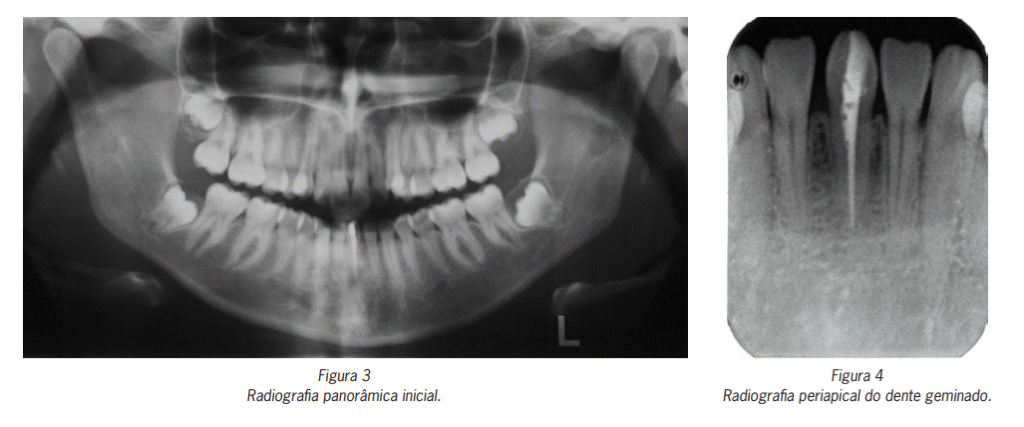

Pela radiografia panorâmica, observou-se a presença de todos os dentes permanentes e estruturas adjacentes com

aspecto de normalidade. Constatou-se a presença de tratamento endodôntico no dente geminado localizado na região

de incisivos centrais inferiores (Figura 3).

Na radiografia periapical, foi observada a presença de um único conduto radicular, tratado endodonticamente, no dente

geminado (Figura 4).